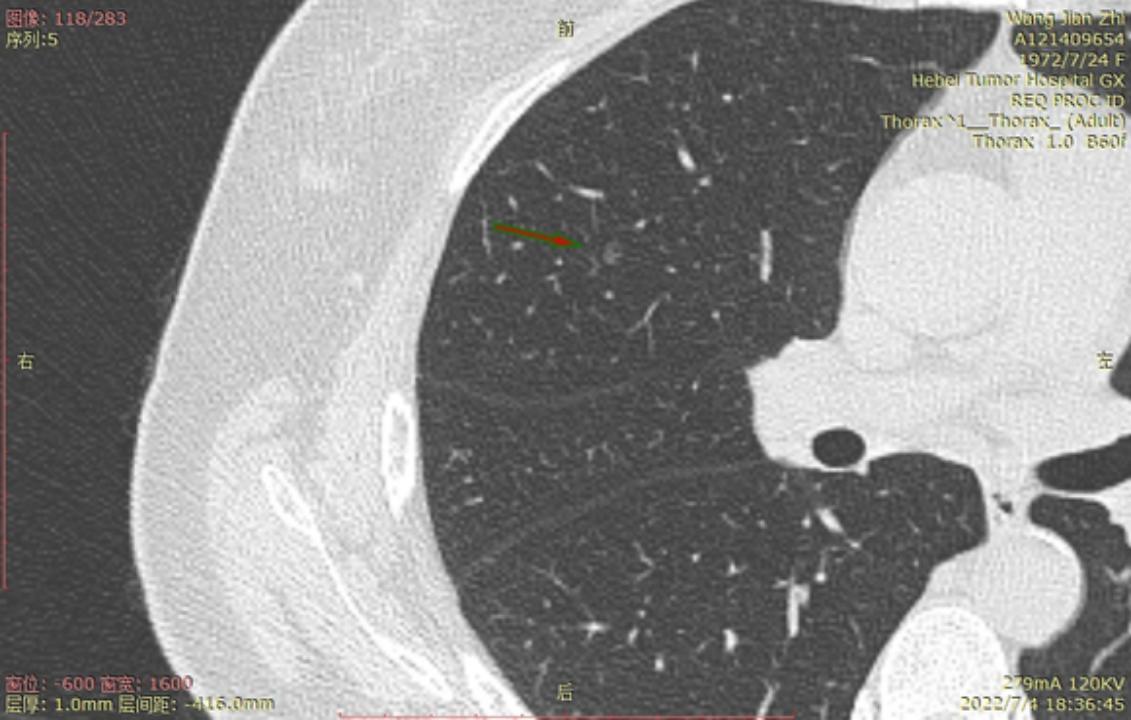

今年6月22号河北省人民医院进行CT检查后,报告双肺多发磨玻璃结节及微小结节以右肺为多,建议六个月后复诊。我于7月3号在河北省四院胸外科就诊,大夫建议复查薄层CT,7月4日CT结果报告示两肺多发结节,部分为磨玻璃密度,建议三个月复查,省四院的主任看了CT后有的建议立即住院手术,有的建议三个月复查,专家意见不一致,后来我看了主任的贴吧,首次发现肺结节先口服莫西沙星,三个月后再复查的贴吧,就没有立刻手术,从7月4日开始口服莫西沙星,现已完成15天疗程。等待复查的这一段时间里,总是担心大的结节已有浸润,请主任给予帮助,看看我的CT,给出我治疗建议,麻烦主任了!

结12

结13